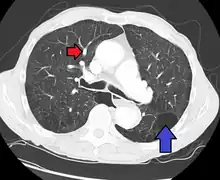

CT scan

Signs of pulmonary hypertension on CT scan of the chest are:

- Enlargement of the pulmonary trunk (measured at its bifurcation). It is, however, a poor predictor of pulmonary hypertension in patients with interstitial lung disease.[59]

- A diameter of more than 27 mm for women and 29 mm for men is suggested as a cutoff.[59]

- A cutoff of 31.6 mm may be a more statistically robust in individuals without interstitial lung disease.[59]

- Increased ratio of the diameter of the main pulmonary artery (pulmonary trunk) to the ascending aorta (measured at its bifurcation).

- Increased diameter ratio of segmental arteries to bronchi. This finding in three or four lobes, in the presence of a dilated pulmonary trunk (≥29 mm), and absence of significant structural lung disease confers a specificity of 100% for pulmonary hypertension.[59]

- Mural calcification in central pulmonary arteries is most frequently seen in patients with Eisenmenger's syndrome.[59]